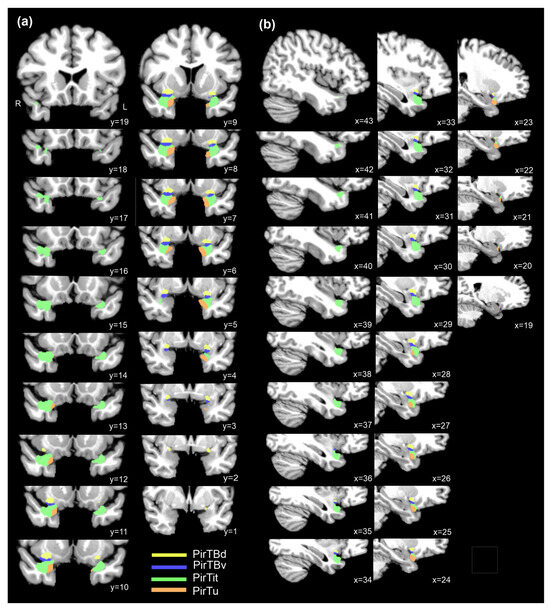

Probabilistic maps of the piriform areas in their rostral and caudal extent revealed a higher degree of topographical variability than in their central position. The maps have a compact form (Figures S1–S4). PirTit had the center of mass at a more rostral position than the other areas, i.e., at the level of the temporal pole (just rostral to the disappearance of Limen insulae), which correspond to y = 9 (left hemisphere) and y = 10 (right hemisphere) in the Colin 27 template. The center of mass had a less-symmetric distribution for PirTu (y = 9 in the right hemisphere and y = 6 in the left hemisphere) and for PirTBv (y = 8 in the right hemisphere and y = 6 in the left hemisphere) (Figure 8). The centers of mass x- and z- coordinates are presented in the Table 4.

Figure 1. Selected sequence of coronal sections in the right hemisphere of the brain pm4 revealing the full rostro-caudal extent of the mesial piriform region and the neighboring amygdala. Abbreviations: PirTBd—piriform temporobasal area, dorsal part, PirTBv—piriform temporobasal area, ventral part, PirTit—piriform temporal area (Incisura temporalis), PirTu—piriform temporal area (uncus). Amygdala: La—lateral nucleus, PL—paralaminar nucleus, BL—basolateral nucleus; APir—amygdalopiriform transition area, Me—medial nucleus, VCod—ventral cortical nucleus, dorsal part, VCov—ventral cortical nucleus, ventral part; fiber bundles: ice—intermediate central fiber masses, iol—intermediate orolateral fiber masses. Macroanatomical landmarks: ambG—ambient gyrus, aps—anterior perforated substance, erh.s—endorhinal sulcus, col.s—collateral sulcus, FG—fusiform gyrus, GS—Gyrus of Schwalbe, it—Incisura temporalis, LI—Limen insulae, phG—parahippocampal gyrus, sa.s—semiannular sulcus, smlG—semilunar gyrus, STG—superior temporal gyrus. Neighboring structures: BnM— basal nucleus of Meynert, Cl— claustrum, Ent— entorhinal cortex, Ins— insula, Tu— olfactory tubercle, PirB—piriform basal area, PirI—piriform insular area, TPrh—temporopolar-perirhinal area (periallocortex), TPir—temporopolar-piriform transition area (periallocortex), Prh—perirhinal cortex (Brodmann area 35, 36), Rb—retrobulbar region.